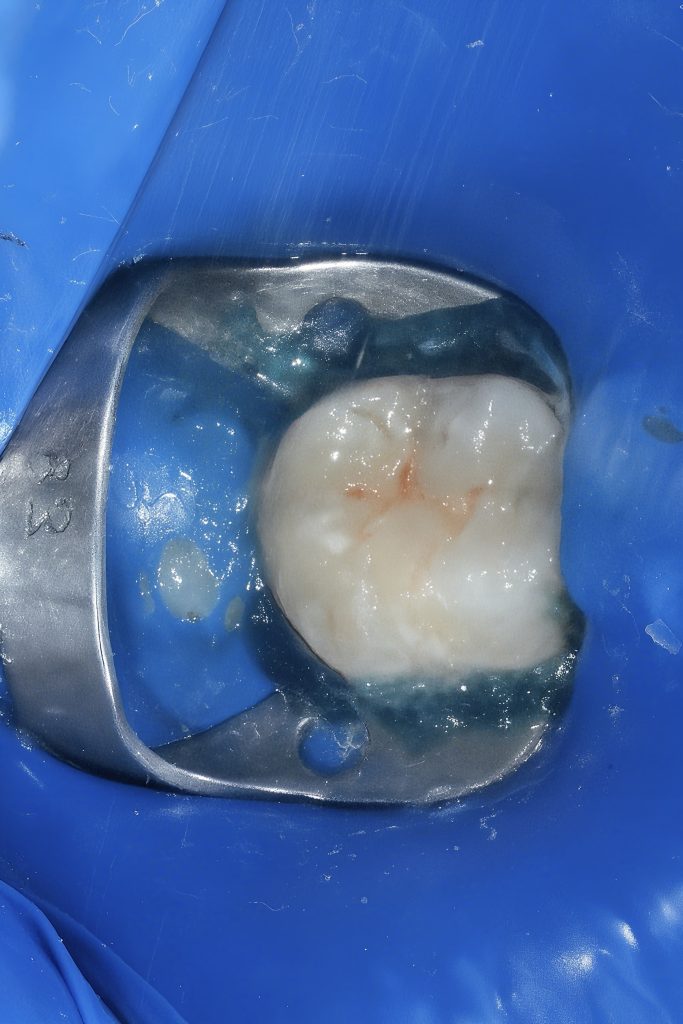

A posterior molar presented with primary occlusal caries confined to enamel and dentin (Fig 1). Under rubber-dam isolation, caries was removed conservatively using a round bur and spoon excavator, preserving peripheral enamel. The cavity design was limited to the carious lesion with no additional mechanical extension.

Selective enamel etching with 37 % phosphoric acid (15 s) was followed by application of universal adhesive (GC G-Premio Bond) and light curing for 20 seconds. This ensured strong micromechanical bonding with enamel prisms and hybrid layer formation within dentin (Fig 2).

- Fig 1: Pre-operative view showing occlusal caries.

- Fig 2: Cavity preparation under microscope isolation.